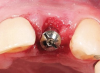

Fig 13. The healing abutment is removed.

Figure 13

Fig 14. The provisional crown is inserted on the day of surgery. Note the height of the gingiva.

Figure 14